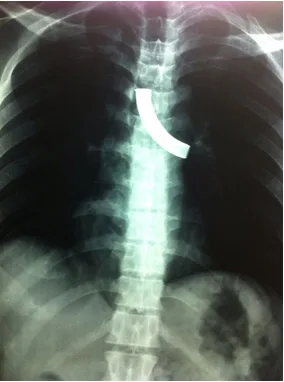

At time of presentation in emergency room (ER) the patient was hemodynamically stable with mild tachypnea (respiratory rate was 22/minute). His oxygen saturation was 97% on air. Neck examination revealed a patent stoma. On auscultation air entry was reduced on left side of chest. Rhonchi were present. A chest X-ray (postero-anterior view) revealed fractured TT in left main bronchus. He was given oxygen inhalation, nebulization and steroids in the ER and then shifted to operating room (OR).